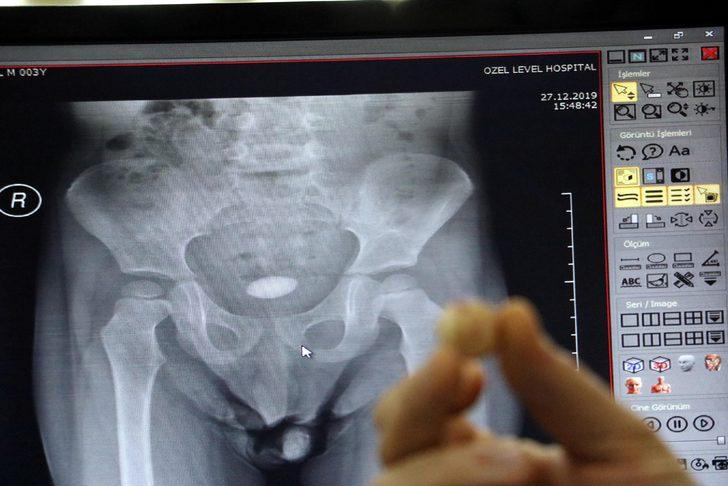

Zonguldak'ta, 3 yaşındaki U.T.'nin, karın ağrısı şikayetiyle gittiği hastanede mesanesinde tespit edilen 3 santim boyundaki taş ameliyatla alındı. Üroloji Uzmanı Dr. Okan Biçgi, bunun çocuklarda nadir görülen bir olay olduğunu belirterek, "İdrar torbasının içindeki taşı aldık. Şu anda ayağa kalktı, dolaşıyor. Şikayetleri büyük oranda azaldı" dedi.

İdrar yollarında rahatsızlık yaşayan U.T., ailesi tarafından önceki gün özel hastaneye götürüldü. Dr. Okan Biçgi'nin muayene ederek röntgenini çektiği U.T.'nin mesanesinde 3 santimetre boyunda taş olduğu tespit edildi. U.T.'nin mesanesindeki taş, dün gerçekleştirilen ameliyatla alındı. Ağrıları geçen U.T., sağlığına kavuştu. Ameliyatın ardından taşı gören U.T.'nin ailesi şaşkınlık yaşadı.

Ameliyatla ilgili bilgi veren Dr. Okan Biçgi, "3 yaşında bir erkek hastamız. Hastanemize idrar yollarıyla ilgili şikayetleriyle başvurdu. Çocuk hastalıkları uzmanımız değerlendirdi ve yaptığımız tahlillerde mesanesinde 3 santimetrelik taş olduğunu tespit ettik. Böbreklerin de değerlendirmesi ve kan analizleri yaptıktan sonra bir operasyon planladık. Bu gibi taşlarda önce enfeksiyon riskini ortadan kaldırmak ve çocuğa en az zarar verecek şekilde bu taştan kurtulmaktır amaç. Biz açık cerrahiyi tercih ettik. Bu delikanlıda yaptığımız ameliyat açık olarak idrar torbasının içindeki taşı aldık. Şu anda ayağa kalktı, dolaşıyor. Şikayetleri büyük oranda azaldı. Bir hafta kadar hastanemizde kalacak ve sonra evine göndereceğiz" dedi.